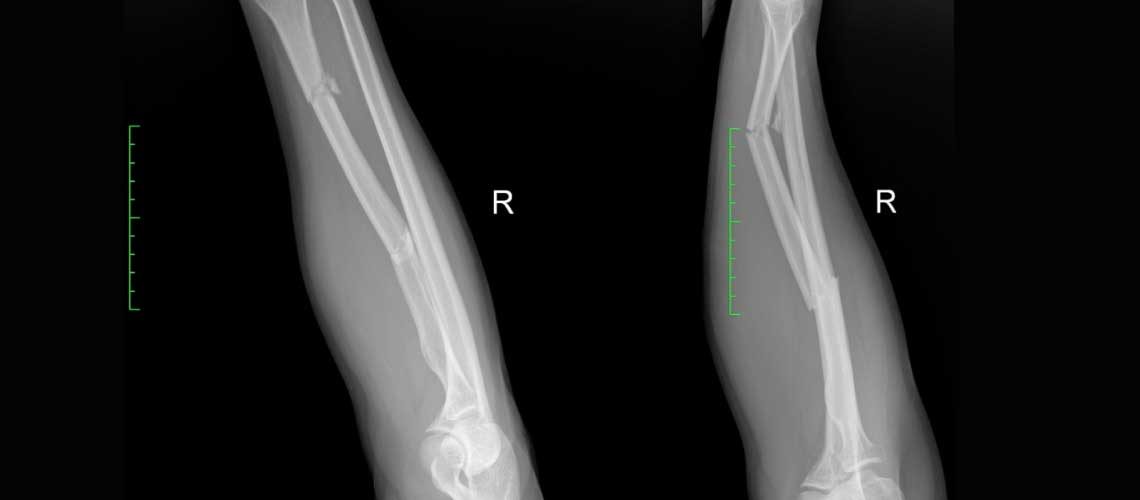

Άνδρας, 43 ετών, υπέστη βαριά κάκωση αντιβραχίου κατά τη διάρκεια αγώνα μπάσκετ. Ο ασθενής μεταφέρθηκε άμεσα στο νοσοκομείο όπου ο ακτινολογικός έλεγχος ανέδειξε διπολικό κάταγμα κερκίδας.

Τα κατάγματα κερκίδας είναι μια από τις πιο συχνές αθλητικές κακώσεις του άνω άκρου και προκύπτουν συνήθως μετά από πτώση και στήριξη στο χέρι. Ωστόσο, τα διπολικά κατάγματα, αυτά που χαρακτηρίζονται από διπλό κάταγμα με αποτέλεσμα να δημιουργείται ένα κεντρικό ελεύθερο τμήμα στο οστό, είναι κατάγματα που απαιτούν ειδική αντιμετώπιση λόγω της δυσκολίας και της ιδιαιτερότητας στην ανάταξη τους.